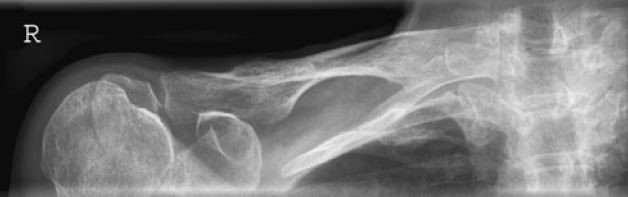

Które badanie zostało zarejestrowane na przedstawionym radiogramie?

Ilustracja do pytania 21

A. Jamy brzusznej wykonane poziomą wiązką promieniowania.

B. Płuc wykonane metodą Przybylskiego.

C. Układu moczowego z użyciem środka kontrastującego.

D. Dróg żółciowych metodą cholangiografii śródoperacyjnej.